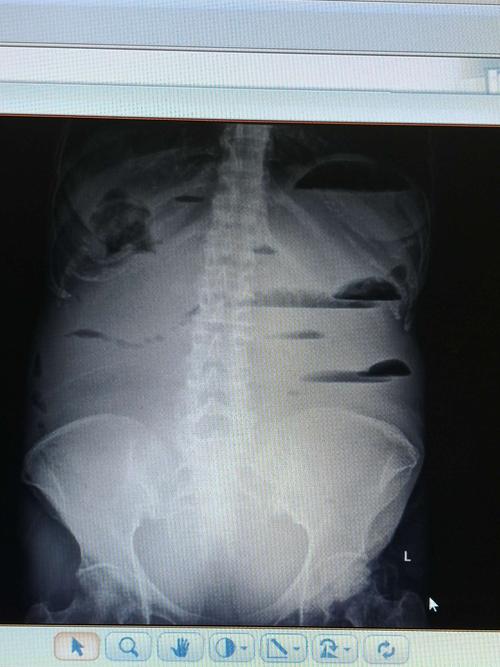

正常腹部平片

正常腹部平片,正常腹部x线平片图

正常腹部平片影像表现